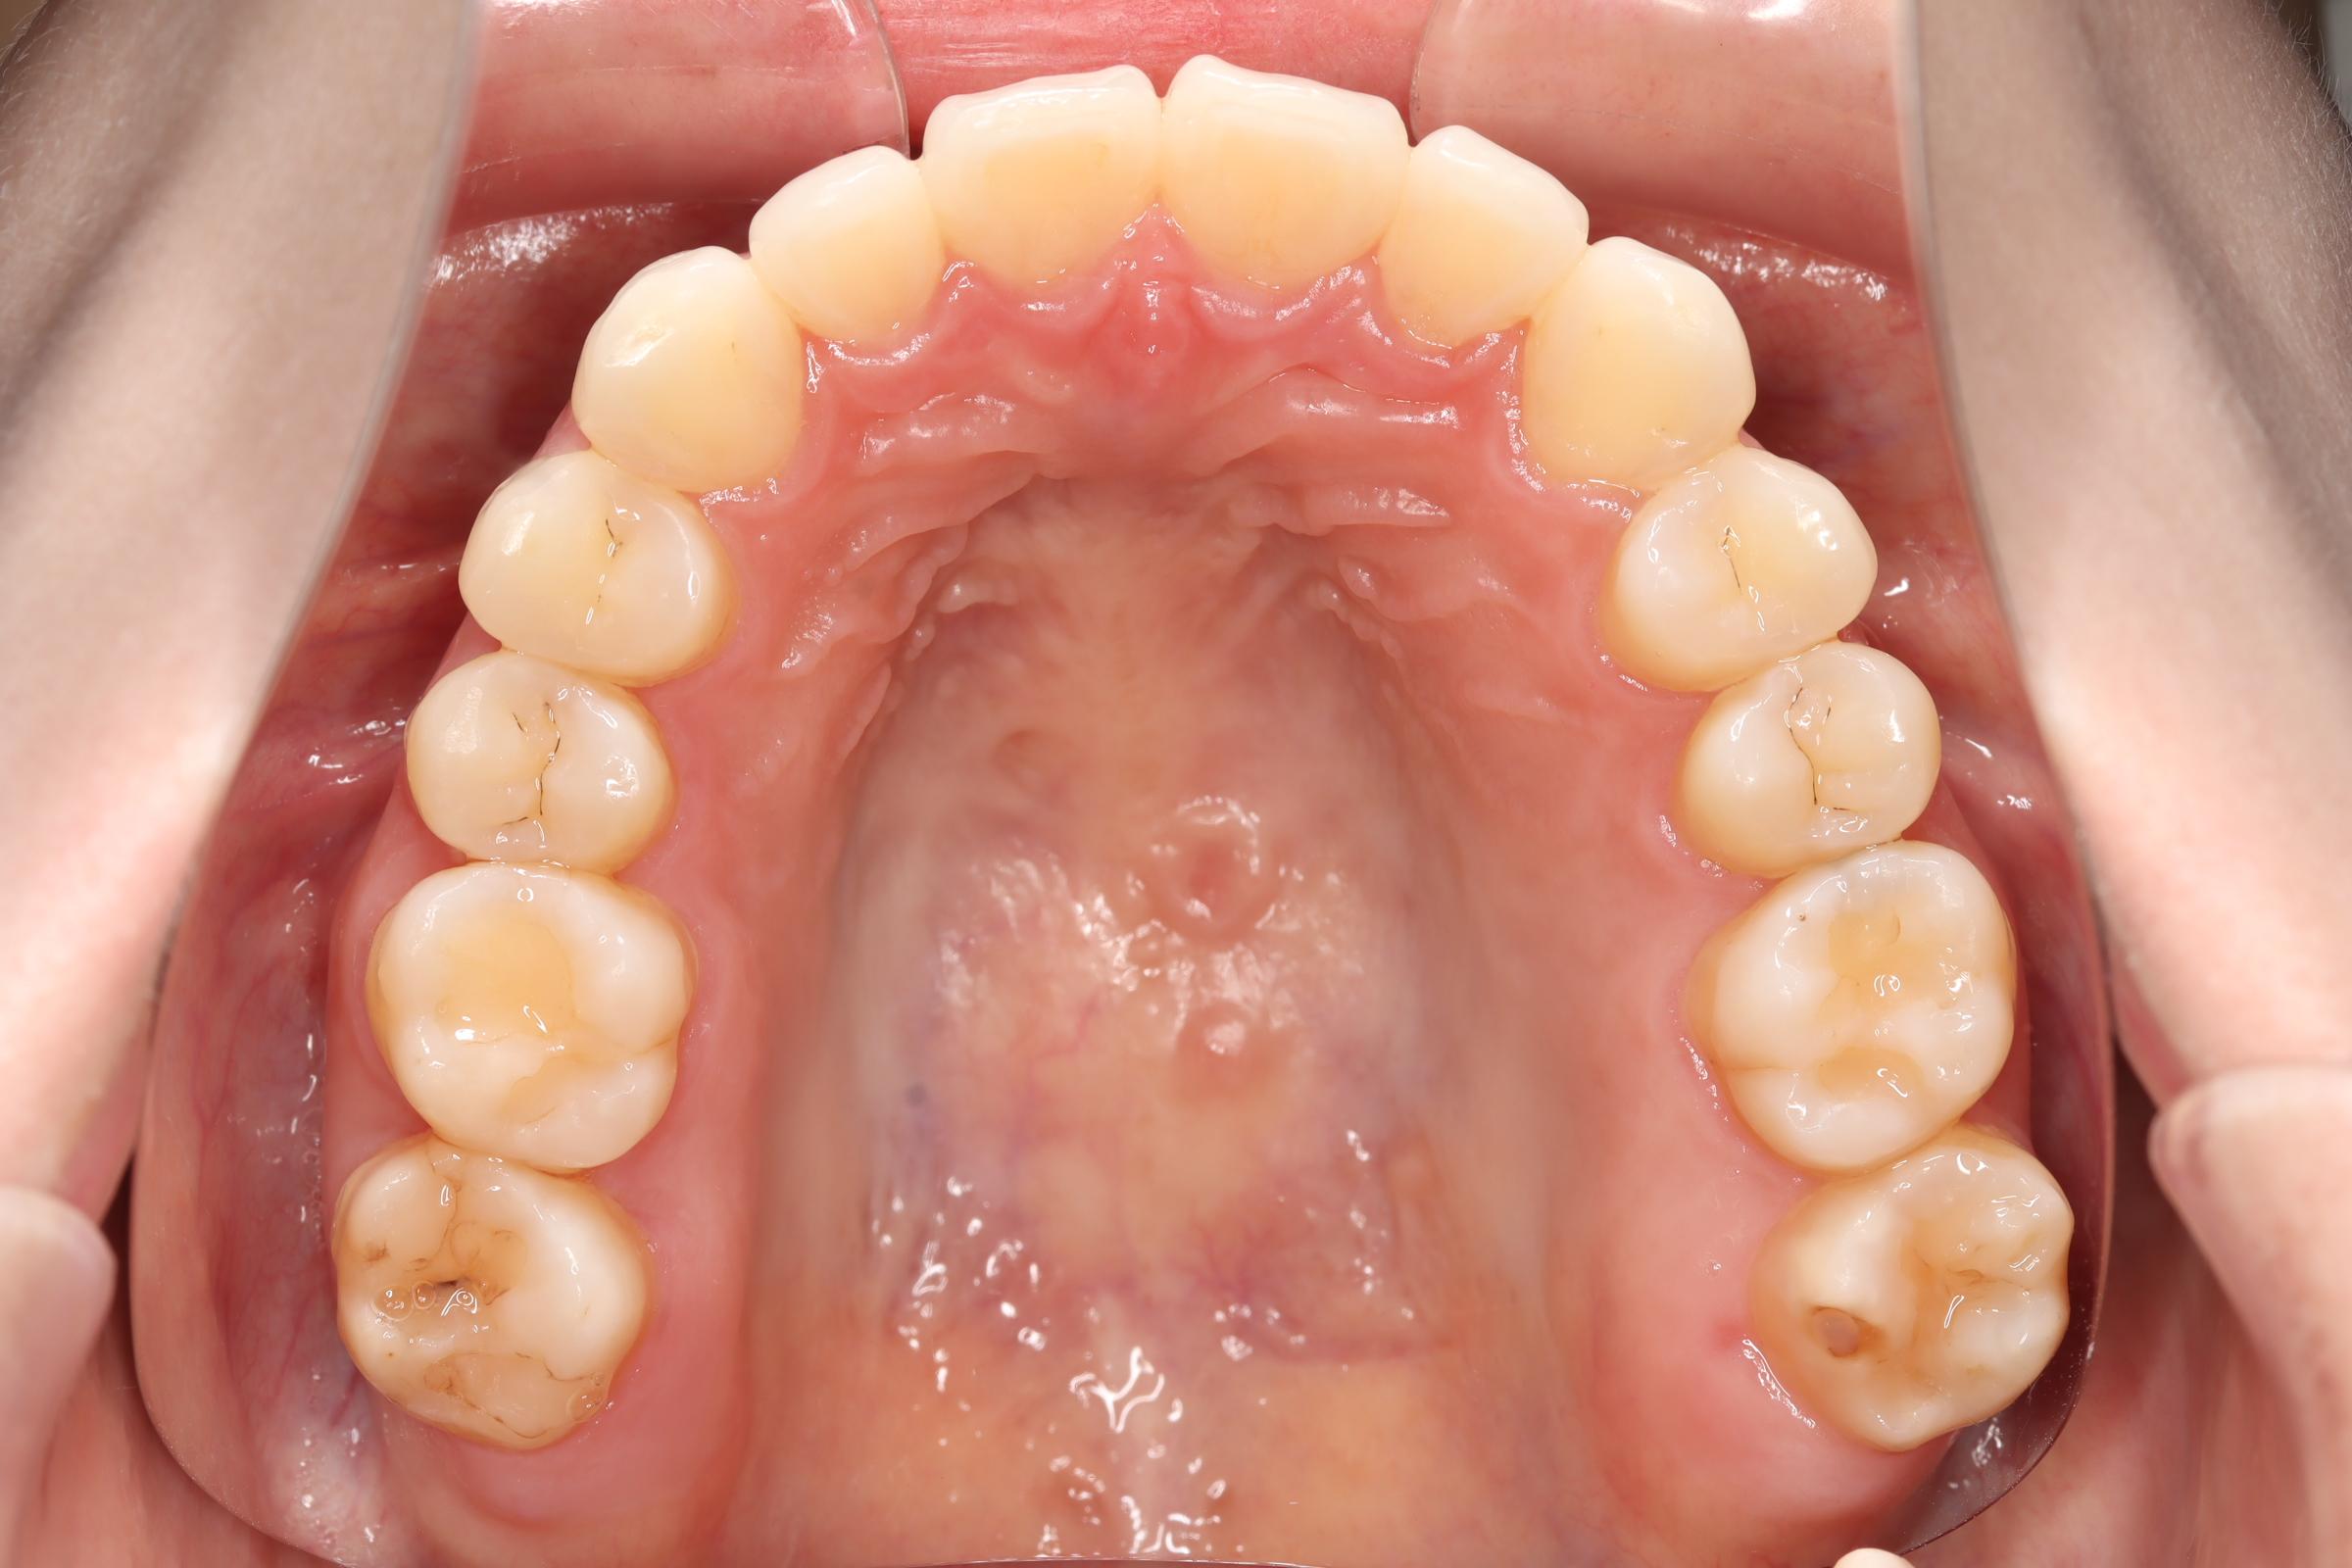

口腔内の変化

![]() | ![]() | ![]() |

| ↓ | ↓ | ↓ |

| 治療前 | 骨格的には受け口の患者さんですが、上顎前歯の唇側傾斜が大きく、患者さんとしては出っ歯だと思われていたパターンです。 元々口元の突出感はほとんどなかったため、歯を抜かずに上下顎ともに歯列を後方に移動させることにより主訴を改善させることとしました。 |